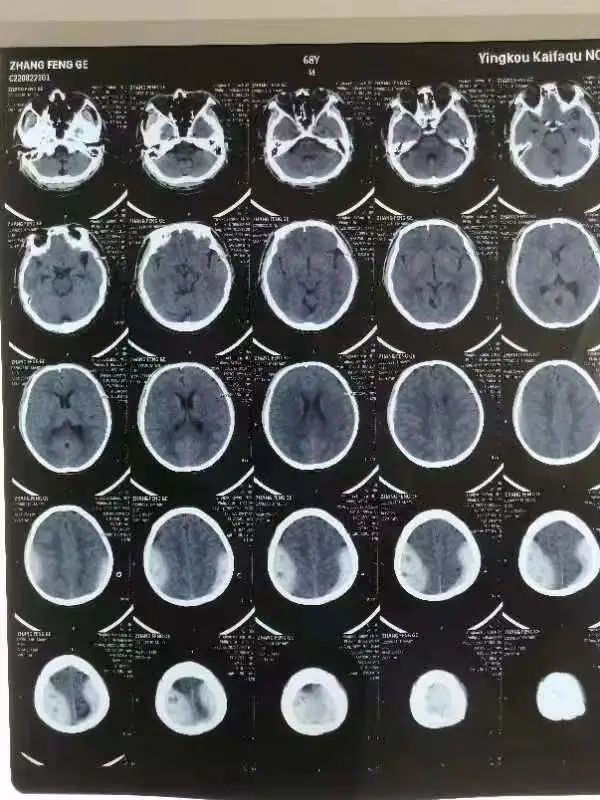

病例一

上矢状窦损伤致硬膜外血肿,两侧出血180ml,保守治疗成功挽救患者生命。

60岁的李大爷,因交通事故伤及头部送到我院就医。入院时病情极其危重,伴有头痛、头晕、恶心,颅脑CT提示为双侧额顶骨、右侧颞骨、左侧枕骨见骨质断裂错位,左侧顶骨轻度向内凹陷。双侧硬膜外出血,脑挫烈伤,蛛网膜下腔出血双侧陈旧腔梗。

一般情况下颅内急性出血在50—70ml左右即可引起脑疝,可李大爷的出血量已经达到了惊人的180ml,必须马上进行抢救。因颅内的上矢状窦是脑内静脉血回流出颅的必经血管,发病急,进展快,短时间内可出现病情严重恶化,手术风险极高,术中患者随时可因颅内大出血危及生命。考虑到种种原因,家属决定放弃手术,采取保守治疗的方式。

(治疗前影像报告)